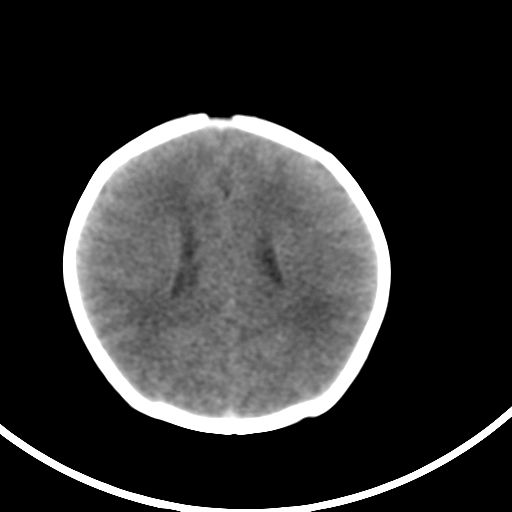

新生儿3天,超过预产期5天剖宫产,有缺氧病史,具体评分不详,现反应差,肌张力低,前囟平,原始反射存在,无苦闹等。

kaolv小脑幕,后纵裂区蛛网膜下腔出血;轻度脑肿胀

矢状窦旁征——支持蛛网膜下腔出血